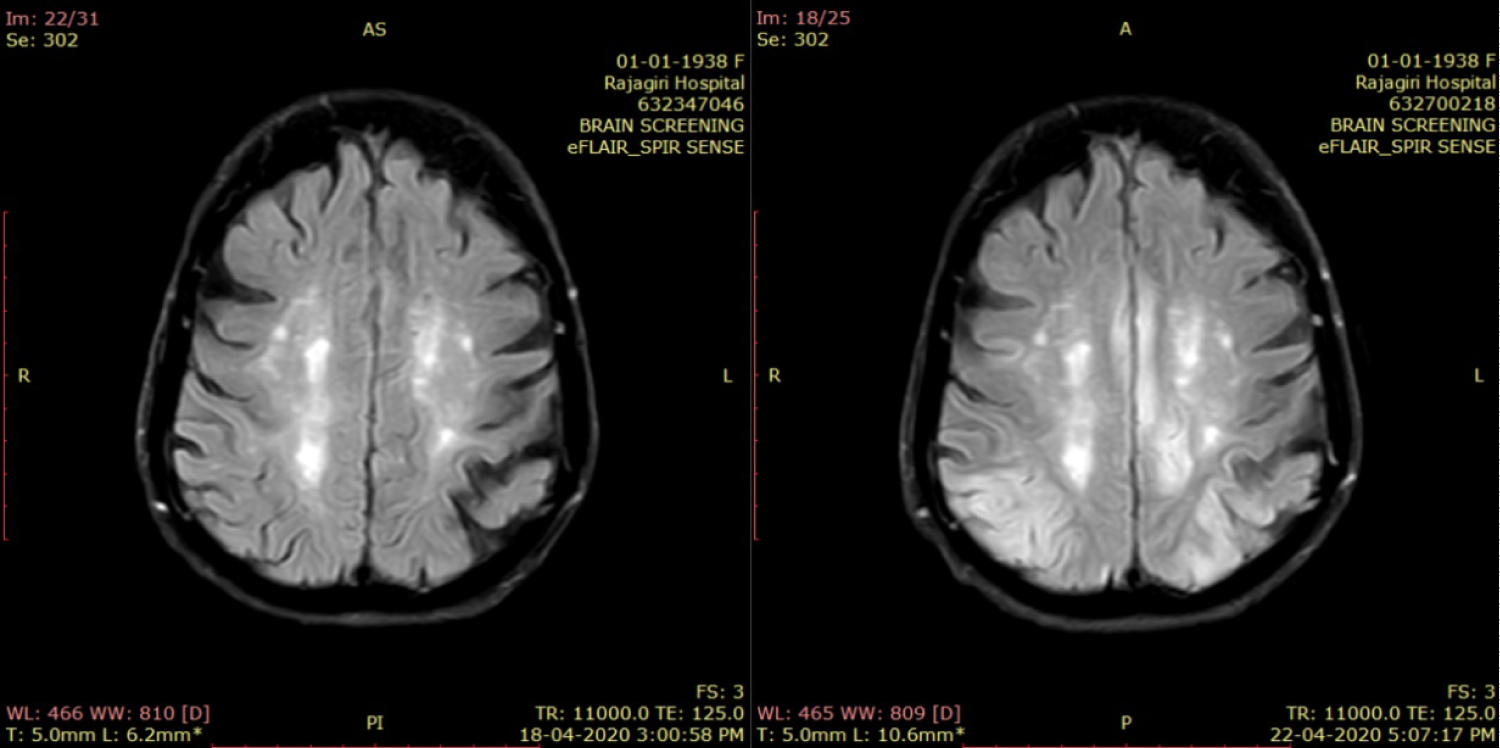

On the second day, she developed focal motor seizure involving left upper limb with further worsening sensorium and vasomotor over activity in the form of uncontrolled hypertension. EEG at that time showed epileptiform discharges in the posterior scalp leads. She was added with intravenous fosphenytoin and lacosamide in addition to leviteracetam. Her inflammatory and infection markers at that time were reviewed and found to be normal. Her metabolic parameters were also within acceptable limits. CSF study was considered but deferred, since her relatives were not keen for it. At that point especially with the history of ingestion of these fruits and intractable seizures, the possibilities of neurotoxicity owing to those were considered. She was given three sessions of one volume plasma exchange in addition to alternate day hemodialysis for better clearance of toxins. But her seizure remained intractable, despite adding propofol, midazolam and ketamine. Further EEG monitoring showed bilateral fronto central and centro temporal spike and wave discharges along with periodic spikes from right fronto central region. We repeated MRI brain 4 days after admission, which showed "interval appearance" of gyriform T2/FLAIR hyperintense signals involving bilateral parietooccipital cortex (left > right), cingulate gyrus and left medial frontal and inferior temporal cortex demonstrating mild restricted diffusion (L > R) suggestive of star fruit neurotoxicity (Figure 2, Figure 3 and Figure 4). Despite aggressive intravenous antiepileptics and other supportive measures we could not control her seizures and she succumbed on the fourteenth day after admission.

Figure 2: T2 FLAIR axial image taken at the level of the lateral ventricles shows asymmetrical hyperintensities involving the cortex of the bilateral occipital lobes as well as in the regions surrounding the occipital horns of the lateral ventricles in comparison with the first study on left. View Figure 2

Figure 3: T2 FLAIR axial image taken at the level of the third ventricle shows asymmetrical hyperintensities involving the cortex of the bilateral occipital lobes as well as in the regions surrounding the trigones of the lateral ventricle in comparison with the first study on left. View Figure 3